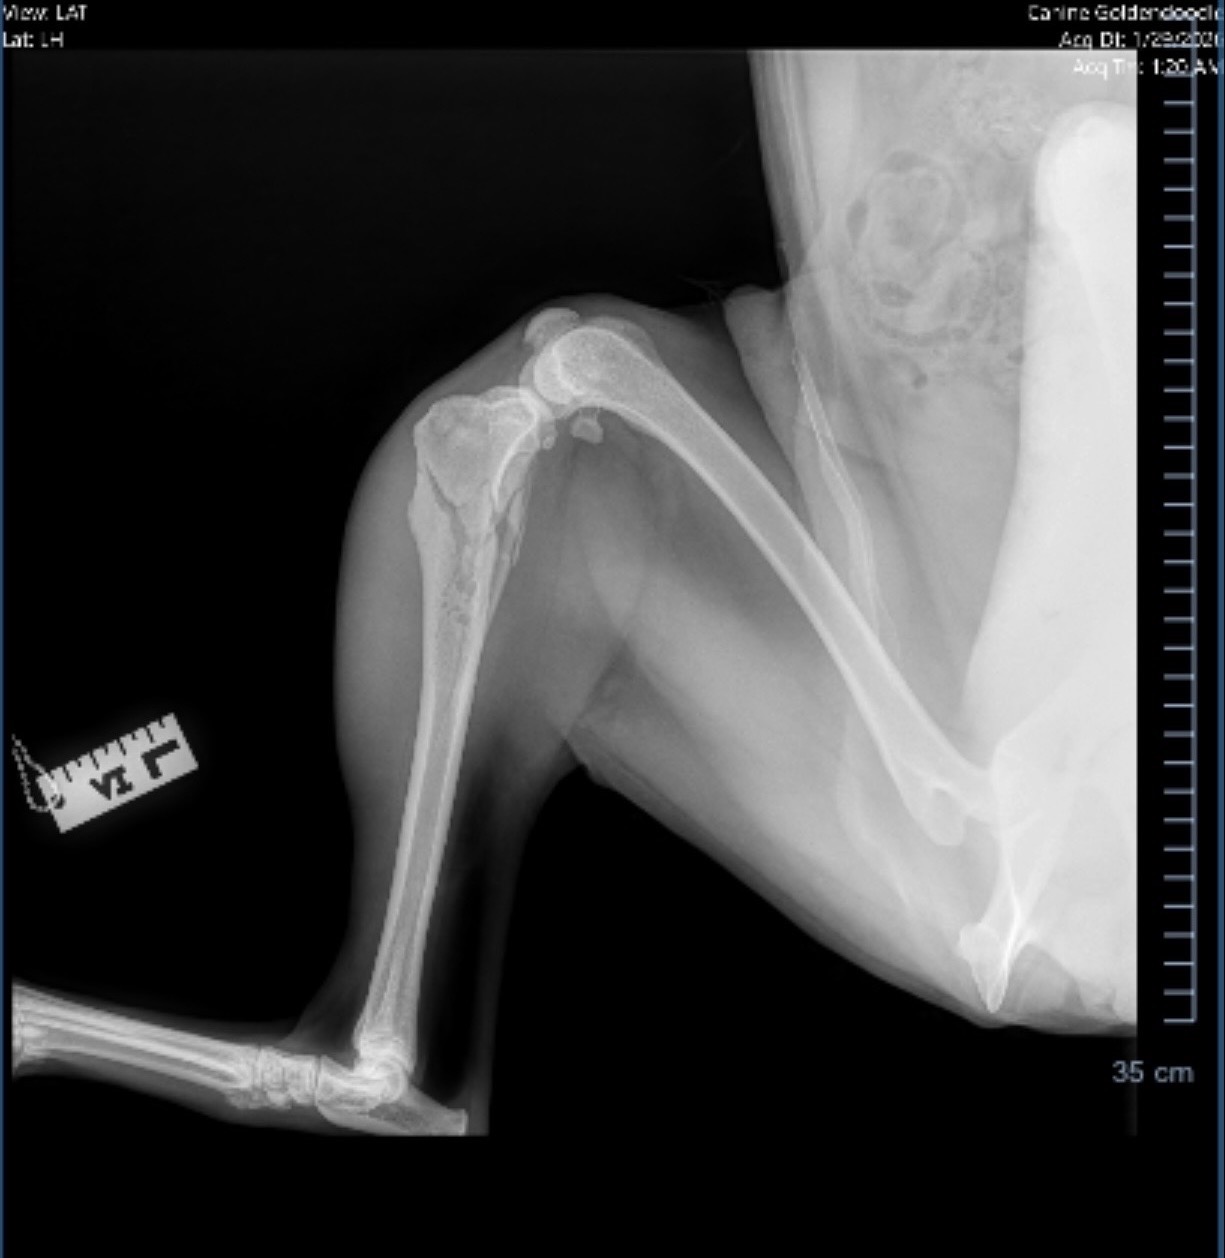

A few days ago, Wrigley’s world was turned upside down when he suffered a shattered leg. I’ve already spent $1,500 on emergency care just to get him stable and on pain management, but the hard part is just beginning. He needs surgery immediately to either repair the fracture or perform a life-saving amputation.

• Surgery (either a plate to repair the bone or an amputation)

• Biopsy to confirm if there is underlying bone disease